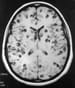

Neuroimaging in neurocysticercosis. Natural history of neurocysticercosis. Top left: This CT scan shows a large occipital active cyst (vesicle phase), many calcifications, and small cortical cysts. Top right: After 18 months, the occipital cyst has been replaced by a calcification and the remaining cysts have disappeared. Bottom left: A single parietal nodular-enhancing lesion (transitional, nodular-granular phase) is shown. Bottom right: Six months later, the lesion has disappeared.